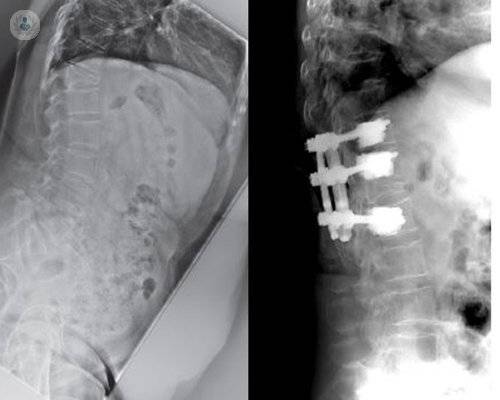

Cirugía de Columna Mínimamente Invasiva

Se preservan las estructuras musculares y nerviosas, que muchas veces son causas de dolor posoperatorio.

Los avances en cirugía de columna permiten una mejor calidad de vida para el paciente

El Dr. Hevia, experto en Traumatología, informa de los avances científicos en cirugía de columna, que permiten tratar con éxito patologías que años atrás requerían de intervenciones mucho más invasivas.

Últimos avances en cirugía de columna

La cirugía de columna es un proceso delicado dentro de la especialidad, ya que es una zona en contacto con tejido nervioso. Los avances permiten minimizar riesgos y complicaciones, así como mejorar la precisión de la cirugía. El Dr. Molina, experto en Traumatología, los detalla.

Cirugía de columna

El raquis o columna vertebral ocupa prácticamente todo el esqueleto en longitud. Sin embargo, su estructura y relaciones anatómicas son diferentes según la zona donde se encuentre la lesión, condicionando las cirugías que pueden realizarse. El Dr. Molina, experto en Traumatología, informa.